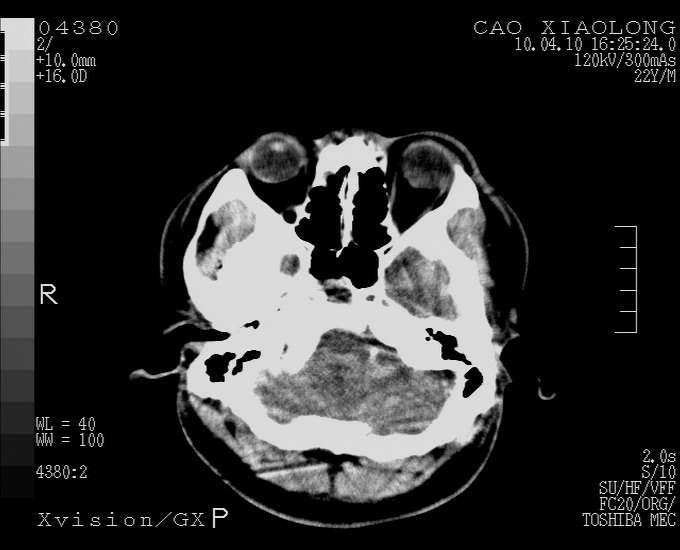

以下是引用随光逐影在2010-4-11 11:00:00的发言:[br]1)左侧额颞顶部硬膜下血肿。2)蛛网膜下腔出血。3)右侧颞顶部颅骨线形骨折。[br][br]20小时后复查:左侧额颞叶脑挫裂伤;左侧额颞顶部硬膜下血肿及蛛网膜下腔出血有吸收表现;右侧颞顶部颅骨线形骨折。[br]